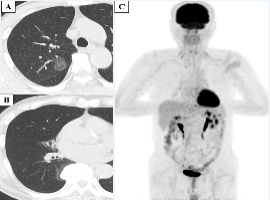

Citation: Motono N, Shioya A, Yamada S, et al. Pulmonary Typical Carcinoid on Right Middle Lobe Hypoplasia: A Case Report and Review of the Literature. Clin Image Case Rep J. 2020; 2(3): 120.